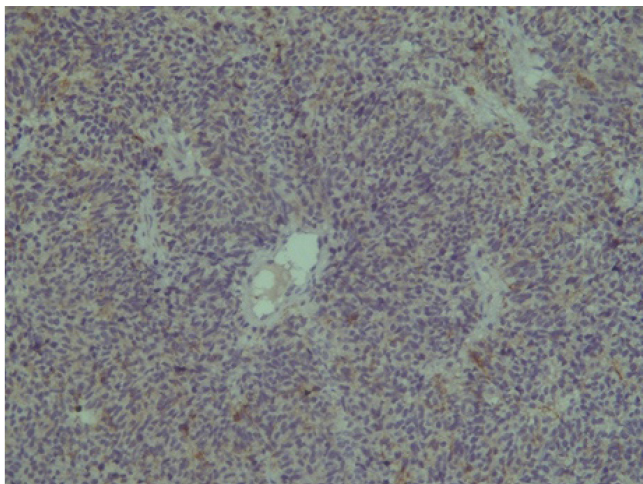

Поэтому при первичном гистологическом исследовании диагноз эстезионейробластомы был установлен только у 6 пациентов (66,6 %), у троих больных (33,4 %) были диагностированы другие формы злокачественного процесса, что не соответствовало клиническим проявлениям. Во всех случаях проводили иммуногистохимическое (ИГХ) исследование. ИГХ-исследование проводили на срезах с парафиновых блоков с использованием антител к Keratin.Pan (AE/AE3), CD45 (Cocktail), Synaptophysin (SP11), ChromograninA (SP12), CD56 (56C04), Ki-67 (30-9), p63 (7JUL)RTU, S100, INI1, CD99 (HO36-1.1). Также выполняли доставку с антителами к EMA (E29), TTF1 (8G7G3/1). В диагностических материалах была отмечена положительная экспрессия Synaptophysin, ChromograninA, CD56, Ki-67 (до 90% ядер), INI1 (рис. 2–6).

Рис. 2. Synaptophysin [SP 11] ×200

Рис. 3. Chromagranin A [SP 12] ×200

Рис. 4. CD 56 [56C04] ×200

Эти результаты иммуногистохимического исследования подтверждают наибольшее соответствие иммунофенотипа опухоли – ольфакторной нейробластоме (G3 по Hyams) М9522/33.